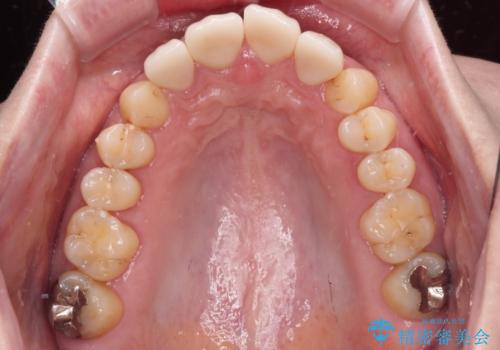

抜歯してからインプラント埋入までには時間がかかるため、その間に下顎左右臼歯の金属のブリッジをオールセラミックへ変えていくこととしました。

継ぎ接ぎだらけの上顎前歯もオールセラミッククラウンにて審美的に改善したいとのことでしたが、捻れが強くあるため、事前に矯正治療で歯列を整えてから、補綴治療を行うこととしました。

目立つ部分の銀歯や気になる変色歯をまとめてきれいに仕上げることができました。